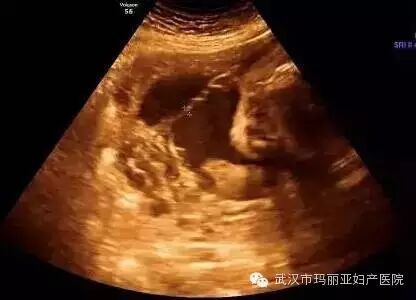

武汉玛丽亚妇产医院引进的世界领先的美国GE-E8四维彩超设备室目前世界上最先进、分辨率最高的彩色超声设备,具有即时立体成像、清晰准确的特点。

它能够多方位、多角度地观察宫内胎儿的生长发育情况,为早期诊断胎儿先天性体表畸形和发育异常提供科学依据。还能对胎儿的体表进行检查,如唇裂、脊柱裂、大脑、肾、 骨骼发育不良等,以便尽早的进行治疗。

玛丽亚美国GE-E8四维彩超排畸成功案例